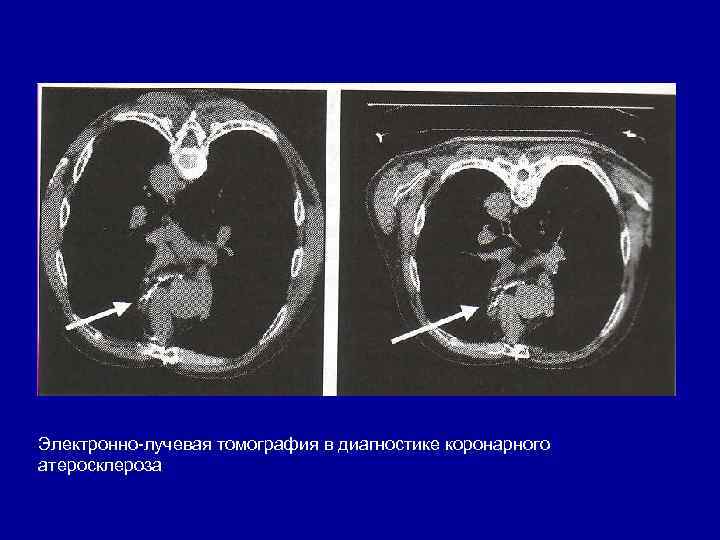

Электронно лучевая томография в диагностике коронарного атеросклероза